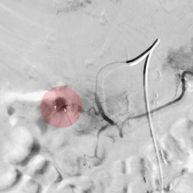

7. Embolisation – Verschluss von Gefäßen

Bei Blutungen durch Gefäßverletzungen, Gefäßmissbildungen, Tumorerkrankungen o. ä kann es sich in der Behandlung notwendig machen, Blutgefäße von innen zu verschließen. Dazu werden über Katheter am Ort des geplanten Gefäßverschlusses kleine Verschlusskörper, Verschlussspiralen oder verschließende Flüssigkeiten injiziert. Bei Tumoren ist auch die lokale Gabe von Chemotherapeutika möglich.